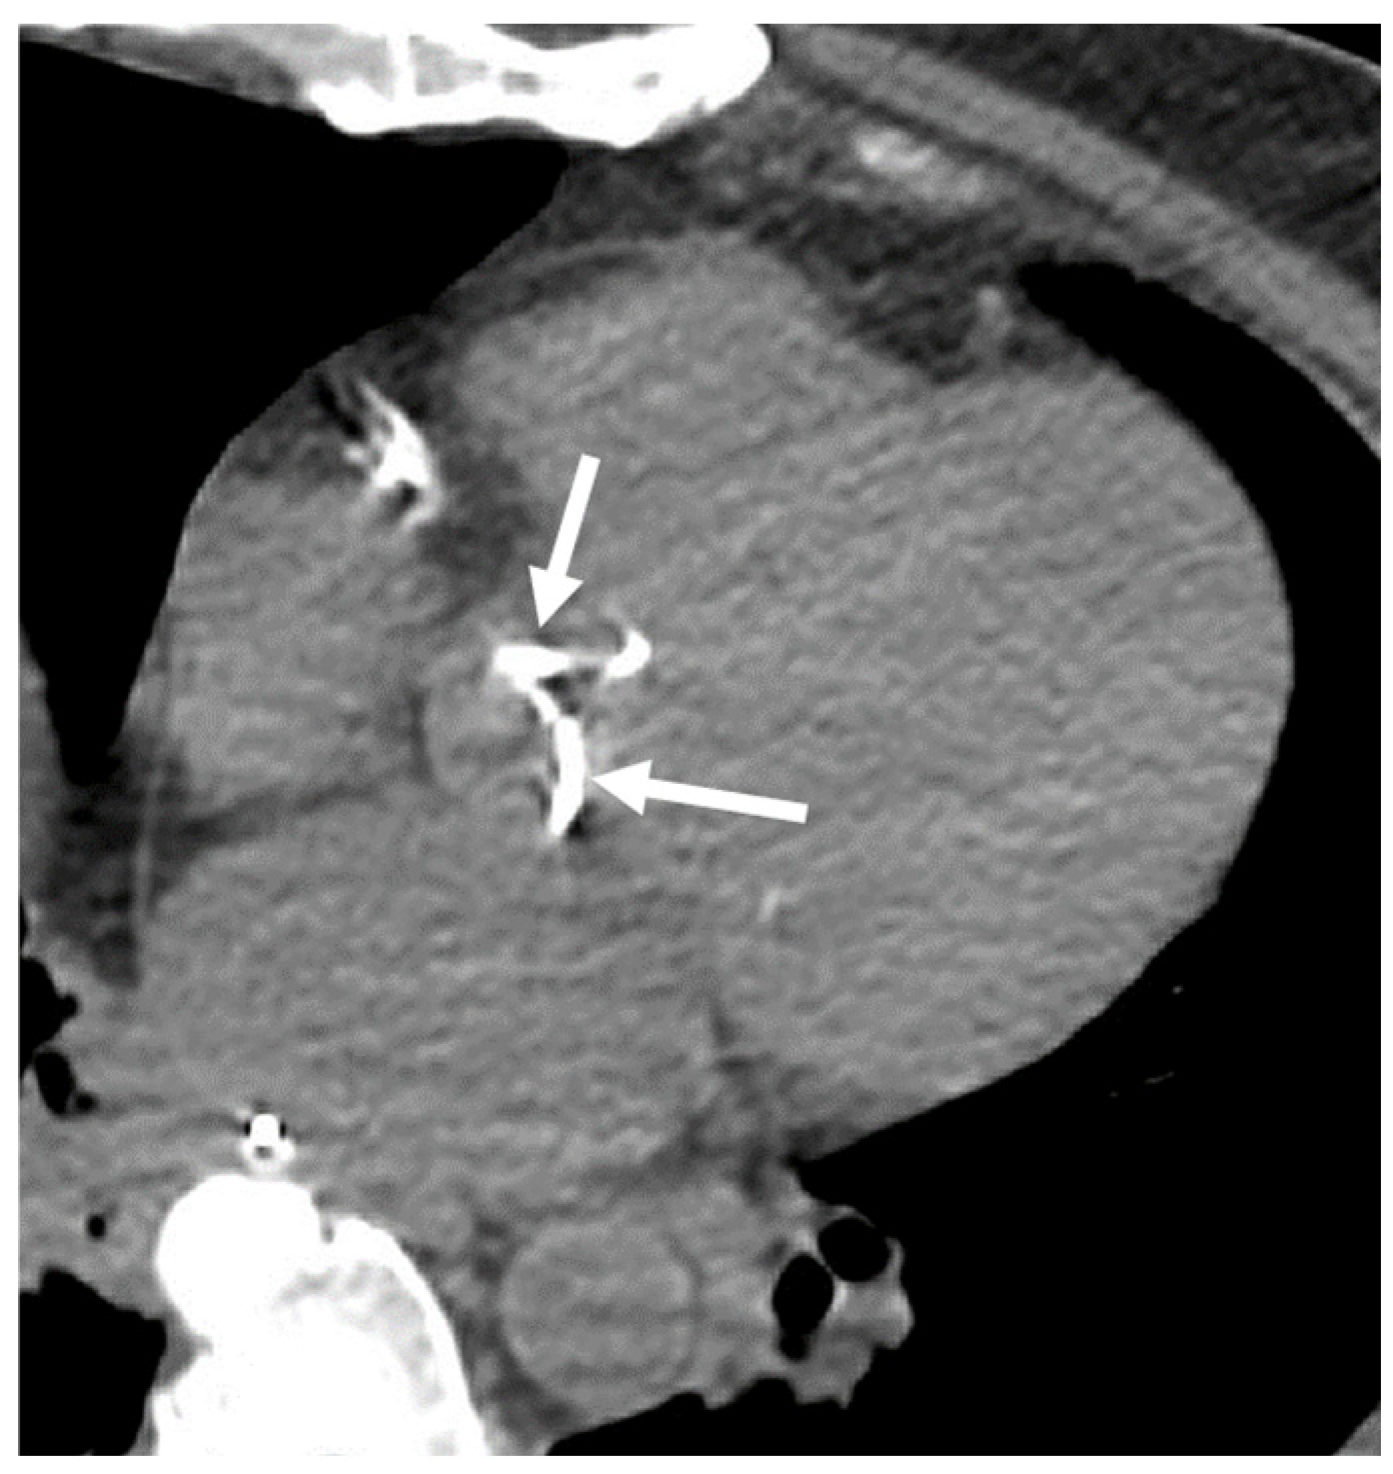

4.3. Aortic Valve Calcification (AVC)

4.4. Pleura and Pericardium